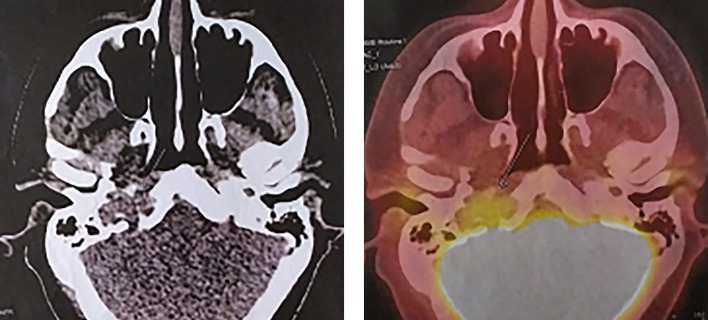

垂体癌(垂体转移性神经内分泌肿瘤)是指已证实有颅脑和/或全身转移的垂体肿瘤。这类肿瘤极为罕见,仅占所有垂体瘤的 0.1%至 0.5%,死亡率很高。在本病例中,一名年轻患者在出现侵袭性复发性分泌催乳素垂体瘤 25 年后被诊断为垂体癌伴颅内转移。标准治疗(转移灶切除、放射治疗、卡麦角林治疗)使病情长期缓解。

Pituitary carcinoma (metastatic neuroendocrine tumor of the pituitary gland) is the pituitary tumor with confirmed craniospinal and/or systemic metastases. These tumors are extremely rare accounting for only 0.1% to 0.5% of all pituitary tumours and are characterized by high mortality. In the presented case, pituitary carcinoma with intracranial metastasis was diagnosed in a young patient 25 years after manifestation of an aggressive recurrent prolactin-secreting pituitary tumor. Standard therapy (removal of metastasis, radiation therapy, cabergoline therapy) resulted in a long-term remission of the disease.